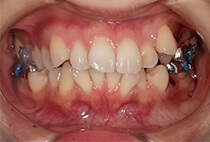

治療後

かみ合わせが整い咬筋の過緊張も改善しました。咬筋の肥大も治ってフェイスラインがすっきりしました。

最終的には美しい歯並びと、安定した痛みのないかみ合わせが実現しました。